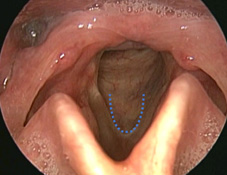

手術加上麻醉的時間,全程約一個小時左右。手術後噤聲期為7天,一個月的恢復期內也需避免胃食道逆流之刺激,以免對剛手術完的聲帶造成傷害。少部分患者術後可能因皮瓣癒合不佳,出現纖維化或有斑痕組織(約5%),可於聲帶局部施打類固醇以改善症狀。除了上述常見病變外,顯微皮瓣手術亦可應用在較特殊的案例,如聲帶沾黏或咽喉狹窄等(如:圖三、圖四),克服傳統手術容易復發再次沾黏的困境。不論是哪一種手術技法,手術後都建議患者配合嗓音治療,可以加速嗓音的恢復並減少日後復發的機會。

圖三、聲帶沾黏,外觀呈U型